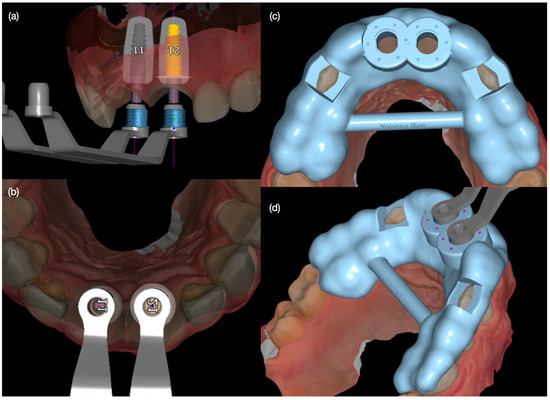

Figure 3. Digital implant planning. (a) Frontal view and (b) incisal view for both implants, and (c) incisal and (d) lateral view of surgical guide.

Diagnostic three-dimensional digital scans (iTero Lumina, San Jose, CA, USA) of the maxilla and mandible were taken, and a traditional facebow record (Artex Facebow, Amann Girrbach, Koblach, Austria) was obtained. Printed models (Phrozen Sonic Mini 8K Resin 3D Printer, Phrozen Technology, Hsinchu City, Taiwan) were then fabricated and mounted on a semi-adjustable articulator (Artex CR, Amann Girrbach, Koblach, Austria). A diagnostic wax-up was performed and mounted in the articulator. The patient also received an intra-oral mock-up with a putty index guide (Elite P&P, Zhermack, Badia Polesine, Italy). An initial CBCT scan and the intra-oral scan were used to digitally plan the implant placement (Exocad DentalCAD, Darmstadt, Germany) and print the surgical guide (Phrozen Sonic Mini 8K Resin 3D Printer, Phrozen Technology, Hsinchu City, Taiwan) (Figure 3). Atraumatic tooth extractions were performed for both maxillary central incisors with the use of a periotome (Anterior Straight PT6, Hu-Friedy, Chicago, IL, USA) and forceps (Upper Anterior Atlas FAF1IS, Hu-Friedy, Chicago, IL, USA), only providing vertical forces, and avoiding any horizontal force (Figure 4). The extraction sockets were cleaned thoroughly with curettes (Universal Curette, Hu-Friedy, Chicago, IL, USA), and the abscess cavity was irrigated with saline solution and chlorohexidine to flush out all the debris and blood. The 3D-printed surgical guide was placed in position, osteotomies were performed, and two implants (3.5 mm diameter; 11.50 mm length, Helix GM, Neodent, Basel, Switzerland) were placed at the planned depth (Figure 5 and Figure 6). An autogenous soft tissue graft was harvested from the palate and positioned on the facial surface of the maxillary left side implant using polyethylene sutures. Interim abutments (Gm Temporary Abutments for Crown, Neodent, Basel, Switzerland) were placed with screw-retained non-occluding interim crowns (Figure 7). The patient had regular follow-up evaluations at 2, 4, 7, and 10 weeks, and at 3 and 4 months, after the implant placement. The provisional restoration was recontoured at week 10, and new sets of interim restorations were made at 3 and 4 months (Figure 8). The patient and clinicians were fully satisfied with the contour obtained with the last set of provisional restorations at 4 months, and it was decided to continue the final stage of the treatment (Figure 9).